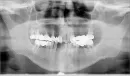

Я начиталась в интернете, что это может быть неврит тройничного нерва. Давала Ибупрофен, Пенталгин, Нейромультивит, что дома было. Завтра обязательно нужно попасть к неврологу. Но вопрос не в этом. Сегодня были у протезиста по записи. Он сказал, что этот неврит может быть спровоцирован в том числе и неправильным смыканием челюстей. Мы думали, что нужно протезировать только выпавшие передние зубы внизу, но как сказал врач нужно снимать все мосты. Удалять внизу крайние коренные зубы, т. к. там полости между корней сверху. Тоже справа крайний зуб сказали на снимке это слева. И может быть второй справа тоже, т.к. там воспаление на корнях, крайний слева. После удаления мостов надо смотреть, какие еще зубы надо удалить. И потом делать съемные протезы, т.к. сейчас неправильное смыкание челюстей. Понятно, что дела не очень, но в 46 лет не хочется жить со съемными протезами.

Прикрепленые фото